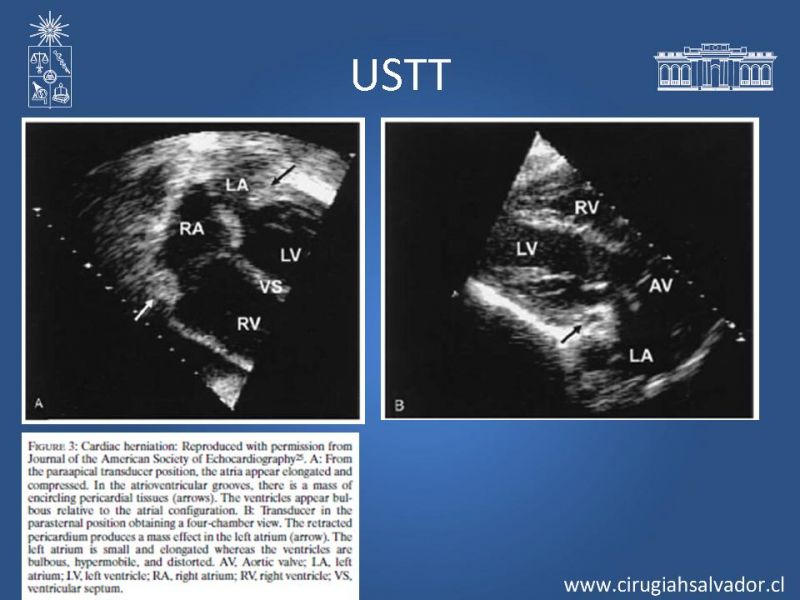

Herniación cardiaca aguda